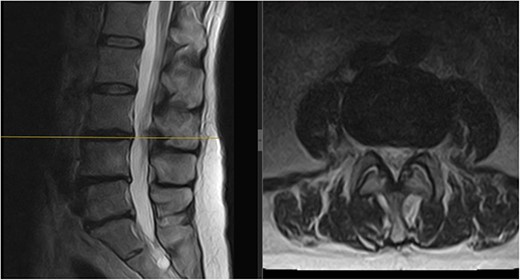

Three months later, the patient noted significant pain reduction. A physical exam revealed an increased range of motion with the patient able to reach her toes whilst flexing forward. No neurological deficits were present. Repeat MRIs showed improvement and resorption of the disc material at L3/L4, relieving the compression on the L4 nerve root (Fig. 3).

Follow-up MRI scan of the lumbar spine: follow-up MRI scan of the lumbar spine performed in March 2023 showing complete resolution of the disc prolapse.